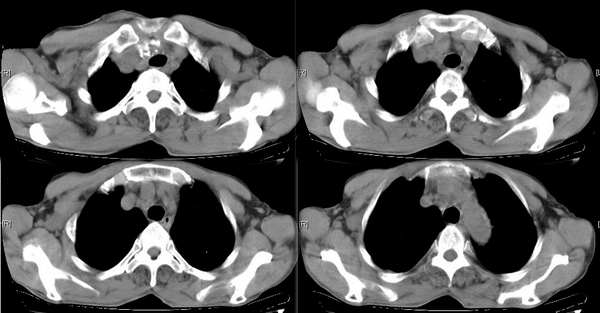

右颈部巨大软组织肿块影,范围较广,上至下颌角,下至颈静脉切迹。其最大层面位于右侧甲状腺区。肿块密度不均,其中有坏死液化区和班片状钙影,增强扫描见肿块实质区有强化。邻近结构挤压移位,部分结构侵蚀破坏,右侧多个颈深淋巴结肿大。两肺弥漫分布小结节影,以胸膜下为主,其大小不等,边缘光整。右侧胸壁亦见软组织结节影,纵隔多个淋巴结肿大及两侧锁骨上淋巴结肿大。

意见:右侧甲状腺癌并两肺、胸壁、纵隔淋巴结、颈深淋巴结、锁骨上淋巴结等广泛转移。

右侧甲状腺腺癌伴颈部纵隔淋巴结转移、纵隔淋巴结转移、肺内多发转移及胸膜转移。

右侧甲状腺癌伴两肺多发转移、纵隔淋巴结转移及胸膜转移